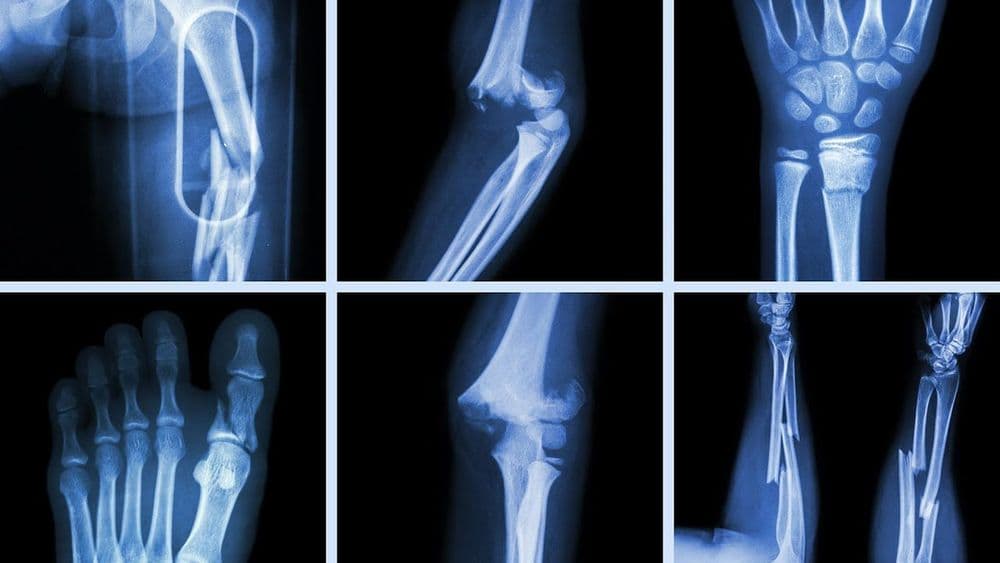

फ्रॅक्चरचे बरेच प्रकार आहेत, पण त्यामध्ये ओपन फ्रॅक्चर आणि क्लोज्ड फ्रॅक्चर हे दोन प्रकार मुख्य आहेत. जेव्हा हाड मोडते परंतु त्वचेवर कुठेही जखमेची खूण नसते तेव्हा त्याला क्लोज्ड फ्रॅक्चर म्हणतात. ज्यावेळी हाड मोडून त्वचेतून बाहेर येते त्यावेळी त्याला ओपन फ्रॅक्चर म्हणतात. ओपन फ्रॅक्चरमध्ये हाडांमध्ये खोलवर जंतुसंसर्ग होण्याचा धोका असतो. हाडे मोडून मोडून त्यांचे लहान लहान तुकडे होणे, हाडांवर विशिष्ट कोनात छेद दिला जाणे, हाडे कमकुवत झाल्यामुळे फ्रॅक्चर होणे, तसेच हेअरलाईन क्रॅक असे फ्रॅक्चरचे अनेक प्रकार आढळून येतात. फ्रॅक्चर कोणत्या ठिकाणी आणि प्रकारचे आहे यानुसार ते किती गंभीर आहे ते ठरते. जर फ्रॅक्चर गंभीर असेल तर त्यावर त्वरित योग्य उपचार करावे लागतात. नाहीतर गुंतागुंत अजून वाढू शकते. यामुळे रक्तवाहिन्या, चेतातंतू यांना इजा पोहोचण्याचा धोका असतो. तसेच हाडांमध्ये व आजूबाजूच्या टिश्यूजमध्ये जंतुसंसर्ग होऊ शकतो. फ्रॅक्चर झाल्यानंतर बरे होण्यासाठी लागणारा काळ हा रुग्णाचे वय, त्याची एकंदर शारीरिक स्थिती, आणि फ्रॅक्चरचा प्रकार यांच्यावर अवलंबून असतो. हा काळ काही आठवड्यांपासून काही महिन्यांपर्यंत असू शकतो.